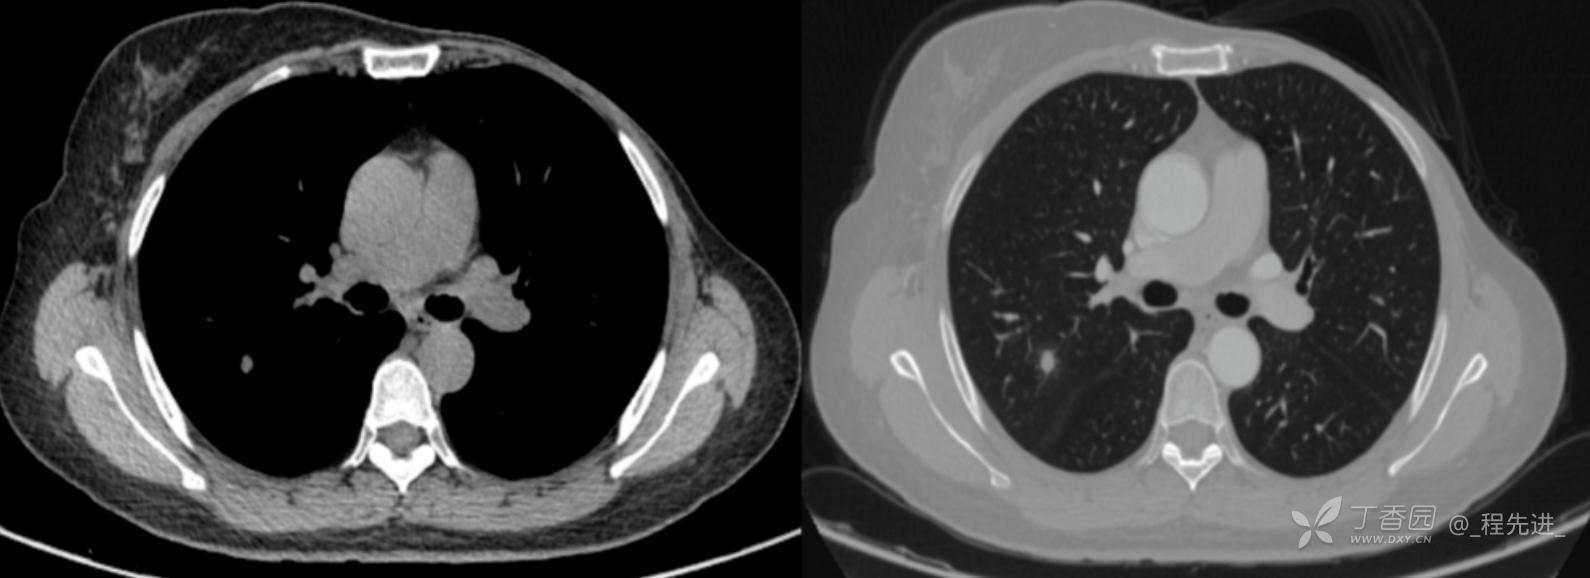

患者性别:女

患者年龄:52岁

简要病史:体检发现右肺上叶结节

既往史:左乳腺癌术后,化疗后

机化性肺炎 (42)

肺结核 (246)